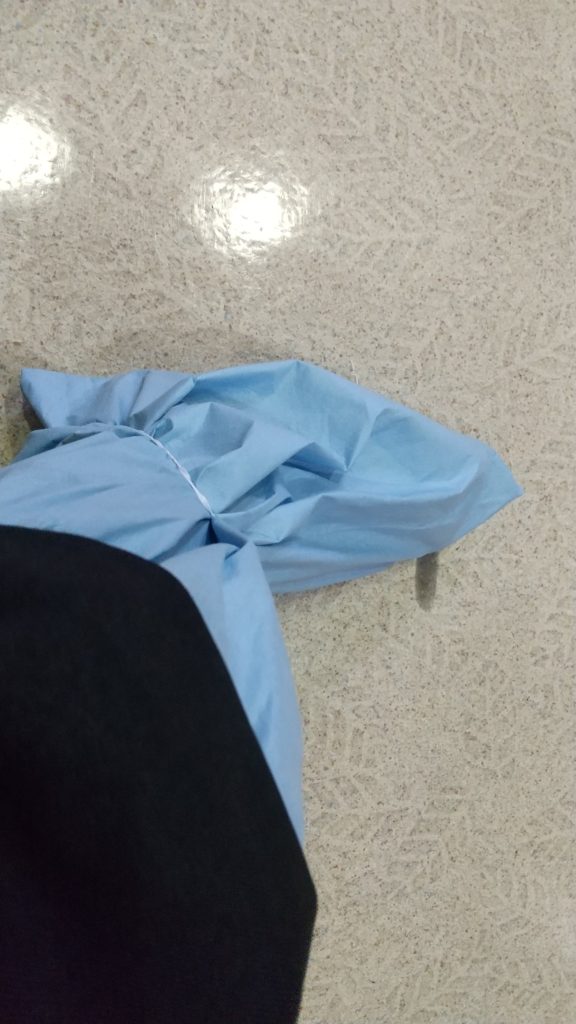

終わったらこんな感じになりました。

術後は靴カバーのようなものを付けていくはずが、備品が足りなかった模様で、急遽、手術室に入る靴カバーのようなものを巻き、支払を済ませ、処方された痛み止めと、化膿止めを院外薬局でもらってから、帰りました。

ここからがまあホテル宿泊スキーなわたし的な本題です。いわゆる焼き鳥串を患部にさしている間は靴は履けてもクロックスでした。こんなふう。

クロックス。いいのだろうか?商品名で述べて。ま、いっか。